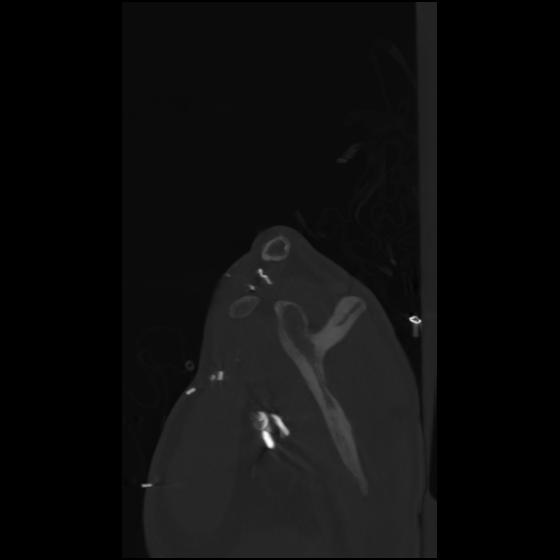

24 ANGIO,CE,Sag-MIP,5.000,ANGIO,Sag-MIP,